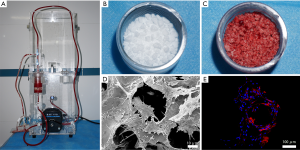

Preparation and characterization of the MSCs/β-TCP composite

The mixture of MSCs/β-TCP was prepared by SECCS, as previously reported (10). Briefly, after the goat was fully anesthetized, approximately 55 mL of bone marrow was taken from the bilateral anterior superior iliac spines. Two mL of bone marrow was taken for nucleated cells and colony-forming units that express alkaline phosphatase (CFU/ALP+) counting. The remaining bone marrow and 6 g of porous β-TCP (1–3 mm diameter, 75% porosity) were placed in the SECCS for preparation of the MSCs/β-TCP composites. After this process, the bone marrow was reserved for the same counting.

To confirm whether MSCs had successfully combined with β-TCP through SECCS, SECCS-processed MSCs/β-TCP particle testing samples were cultured in Minimum Essential Medium (α-MEM) supplemented with 10% fetal bovine serum at 37 °C in 5% CO2 for 2 weeks. The particles in the samples were then observed by scanning electron microscopy (SEM) and a confocal laser scanning microscope. Before the observation by SEM, the particles were subjected to glutaraldehyde fixation, critical point drying, and then metal spraying. For detection by the confocal laser scanning microscope, the samples were fixed with 4% paraformaldehyde and incubated with 5% Triton-100 for 5 minutes, followed by incubation with rhodamine at room temperature in the dark for 40 minutes and then with 4',6-diamidino-2-phenylindole for 5 minutes.

Biological evaluation of the MSCs/β-TCP prepared by SECCS and the counting of replanted cells

The working SECCS is shown in Figure 4A, and SECCS processed the porous β-TCP particles (Figure 4B) to prepare the MSCs/β-TCP composites (Figure 4C). After the MSCs/β-TCP test samples were cultured in vitro for 2 weeks, the cells were observed to adhere to the inner wall of the β-TCP and to have fully spread (Figure 4D,E).

The osteogenic ability of bone fillers is the key to bone defect repair. Since autologous bone grafting, which currently is the gold standard for bone grafting treatment, has some disadvantages, such as limited supply and bone-collecting–related complications, finding bone substitutes with similar osteogenic ability has always been an important goal in orthopedic research (19). Bone marrow MSCs are indispensable for bone repair (20,21). Many studies have confirmed that the use of MSCs with bone substitutes can effectively promote the bone repair effect (22-24). The SECCS we developed previously can rapidly incorporate screening, enrichment of autologous bone marrow MSCs, and generation of composites with porous bone substitutes intraoperatively. These composites have shown superior osteogenic effects in animal models and clinical patients (10,25). In this study, the number of MSCs in the bone marrow was significantly decreased after treatment with SECCS, indicating that MSCs successfully adhered to the porous β-TCP (10). From the testing particles, the adhered MSCs were widely distributed on the inner wall of the β-TCP and fully spread. The number of bone marrow MSCs replanted is an important factor in determining the effect of bone repair (26,27). In this study, each goat was replanted with approximately 31,321.7±22,554.7 MSCs on average in the MSCs/β-TCP–filled group. In the reported studies on bone tissue engineering, most of the implanted MSCs were obtained through in vitro culture, and the number of transplanted MSCs often reached millions, which was much higher than that achieved in this study (22,23). In this regard, we believe that SECCS has the following advantages over in vitro culture technology that outweighs its relatively lower number of replants. Although the number of MSCs expanded in vitro was huge, they originated from a small number of primary cells. In terms of replanted primary MSCs, SECCS showed an overwhelming advantage. Since MSCs will inevitably undergo replicative senescence during in vitro culture, the proliferation and differentiation ability of MSCs will be reduced to a certain extent after expansion, whereas the MSCs replanted by SECCS retain their original ability (28,29). Second, the bone marrow MSCs that expanded in vitro experienced sudden changes in the living environment after implantation into the body, potentially inhibiting cell viability. However, the cells replanted by SECCS were not cultured in vitro, circumventing this inhibitory factor.